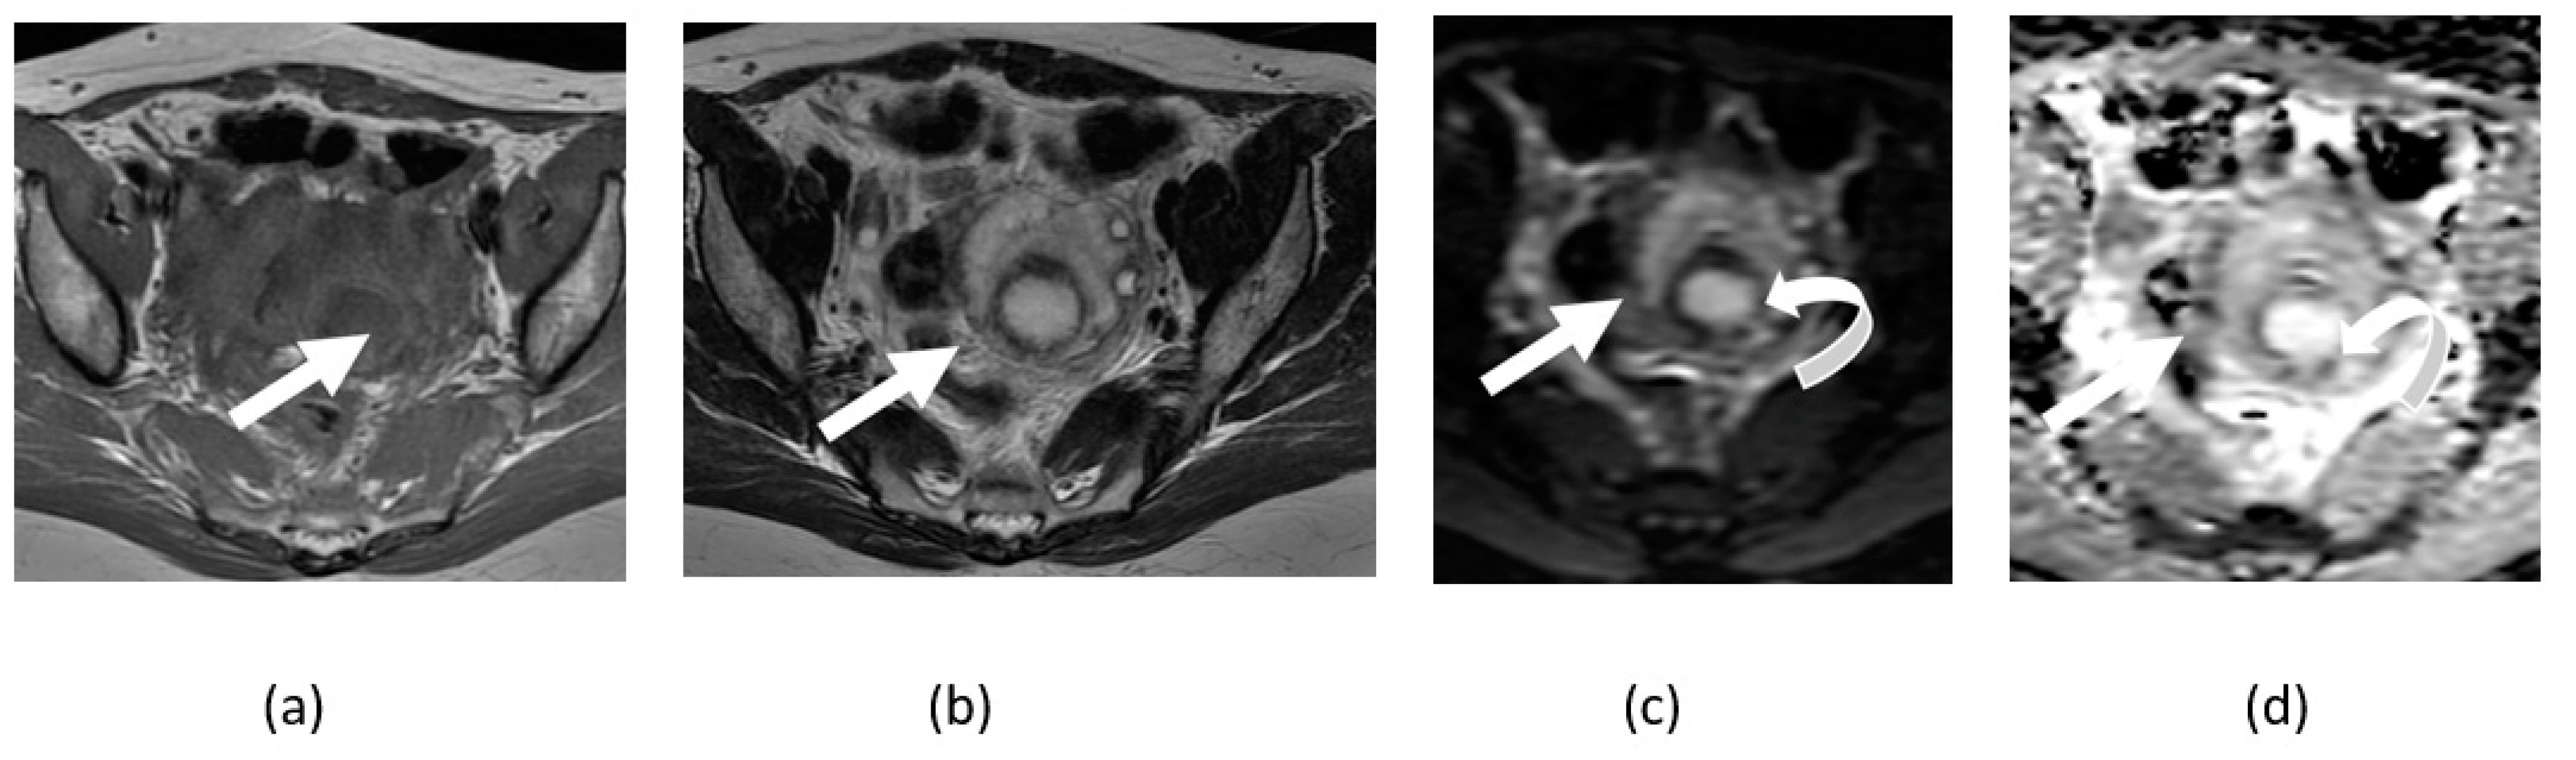

5.1. T2 Shine-Through Effect

5.2. T2 Blackout Effect